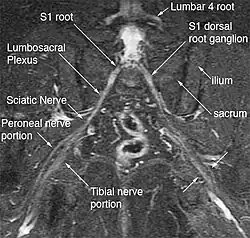

Bilateral magnetic resonance neurography of the sciatic nerves

The general workup involves excluding lumbar, pelvic, and hip pathologies, physical examination, magnetic resonance neurography (MRN) imaging, and diagnostic injections. The use of MRN and diagnostic injections are relatively new diagnostic tools that allow making precise diagnoses where standard diagnostic modalities has failed.[3] Nerve testing such as EMG and NCS can be done but there is little evidence it's helpful.[2] Differential diagnoses (different conditions with similar symptoms) include pudendal nerve entrapment, ischiofemoral impingement, greater trochanter ischial impingement, and ischial tunnel syndrome.[1]